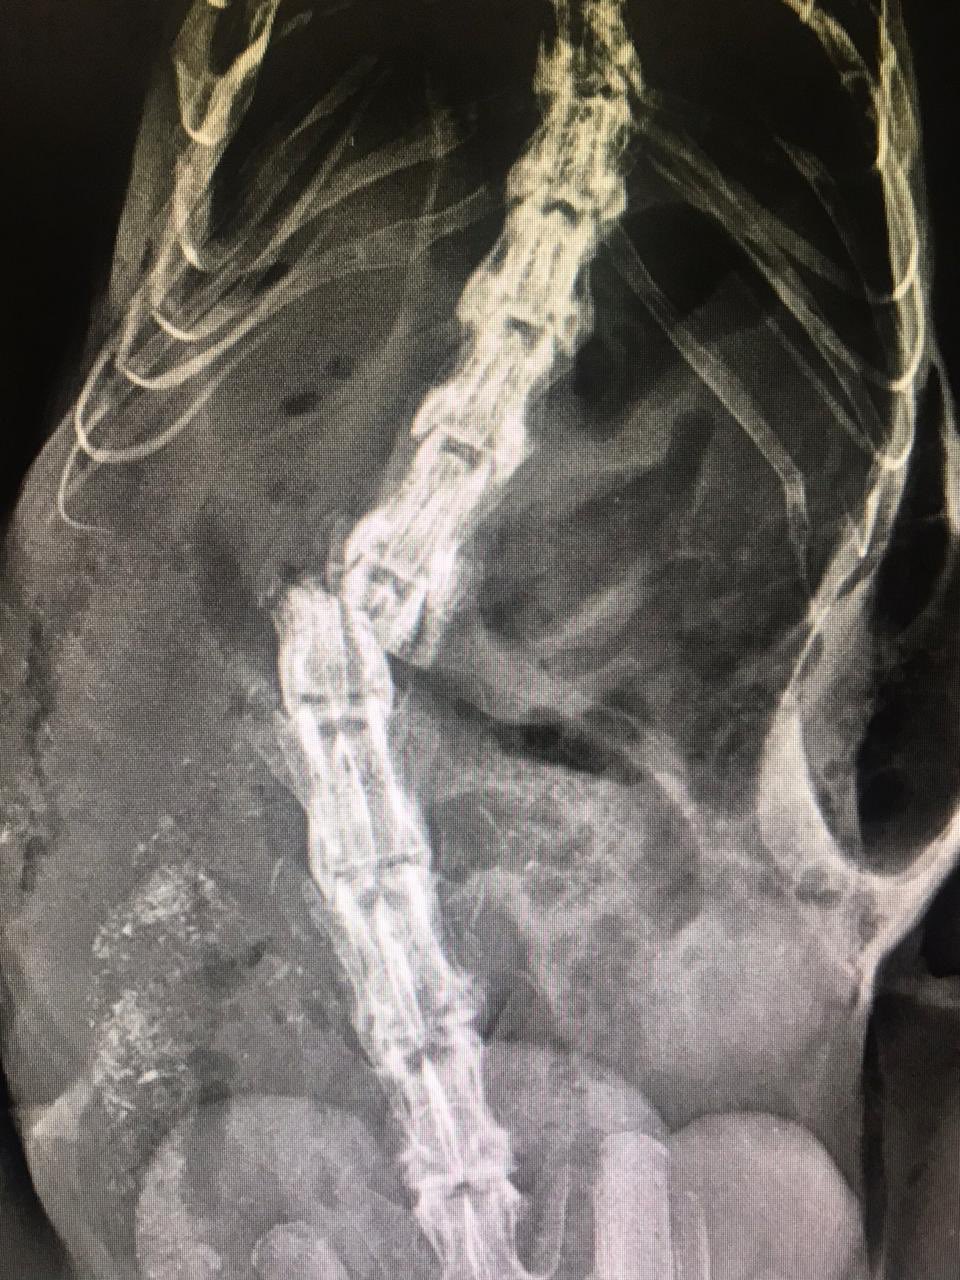

El 10 de abril también se registró un ataque de humanos a una zarigüeya en el Oriente. Aunque fue trasladada hasta Medellín, una radiografía determinó que no podría caminar nuevamente. Para evitar su sufrimiento tuvieron que aplicarle la eutanasia.